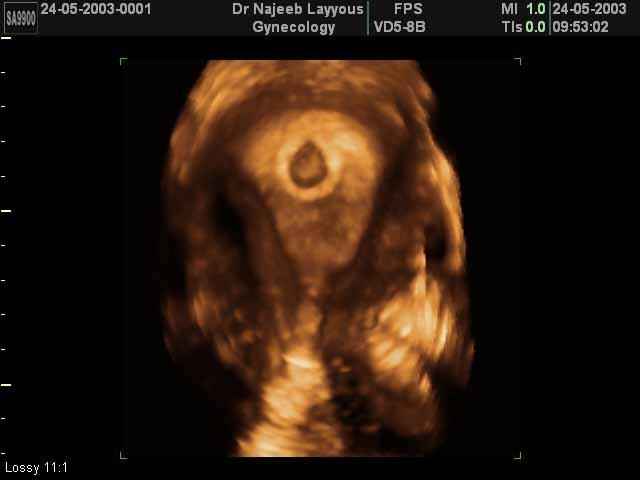

- 3D Photos Ecographie du Premier Trimestre

3D Photos Ecographie du Premier Trimestre (Photos d’échographie de tôt grossesse)| Dr N Layyous